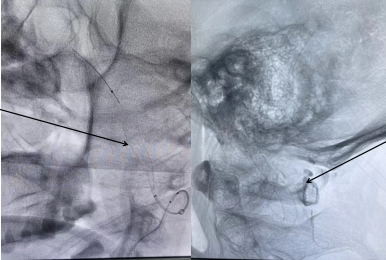

术后

术后患者感觉疼痛症状消失,第一日即可饮食,下床活动。第三日复查头颈CTA,贴壁良好,血流通畅,患者颈部疼痛基本消失,现已顺利出院。